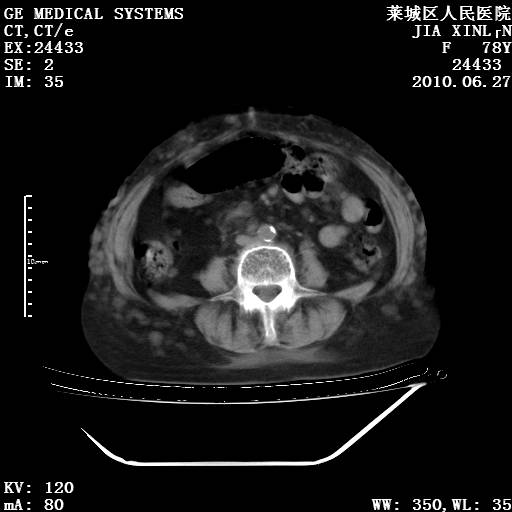

以下是引用胡宇在2010-7-2 19:11:00的发言:[br]神经纤维瘤的特点为:肿块呈多发性、数目不定,少的几个,多的可成百上千难以计数。小的如米粒,大的似拳头,甚至可达十数公斤以上。可松弛地悬挂于皮表,皱褶及松弛可致畸形明显。神经纤维瘤沿神经干的走向生长时呈念珠状,或蚯蚓块状形结节。此外神经纤维瘤皮肤可出现咖啡斑,大小不一,形如雀斑小点状,或大片状,分布与神经纤维瘤肿块的分布无关。肿瘤数目不多的患者,皮肤色素咖啡斑状沉着是纤维神经瘤的重要诊断之一。 本病多发于躯干,有时出现于四肢及面部,患者常合并许多疾病应予重视加以区别。 [br] [br] [br] [br]lyb999说 [br]